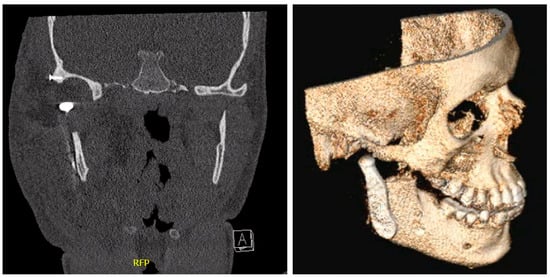

2.1. Clinical Findings and Diagnostic Assessment